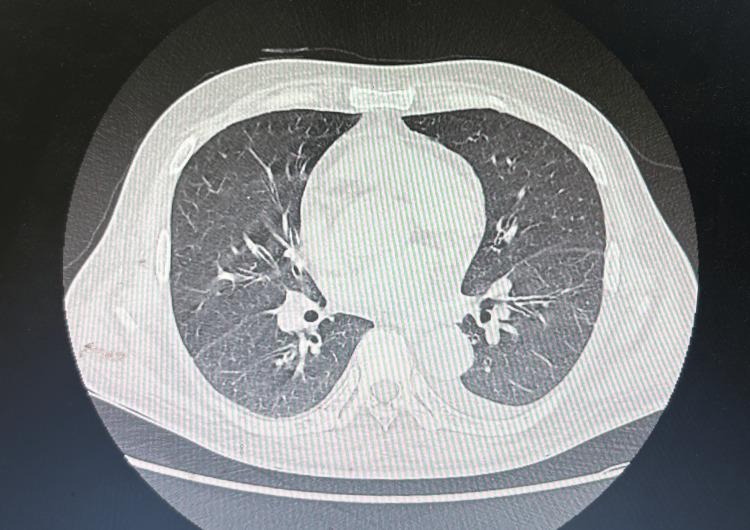

Lactic acidosis is a rare but severe complication of B-cell lymphoma, often associated with rapid disease progression and poor prognosis. We present a case of a 60-year-old male admitted with fever, splenomegaly, hemophagocytic tendencies, and lactic acidosis. The patient underwent several dialysis sessions before bone marrow flow cytometry finally confirmed B-cell lymphoma. However, hyperlactatemia persisted and recurred. The case underscores the challenges in diagnosing lymphomas with atypical presentations and emphasizes the critical role of timely bone marrow analysis. Additionally, the paper discusses the association between B-cell lymphoma and lactic acidosis, highlighting the importance of early recognition and intervention.